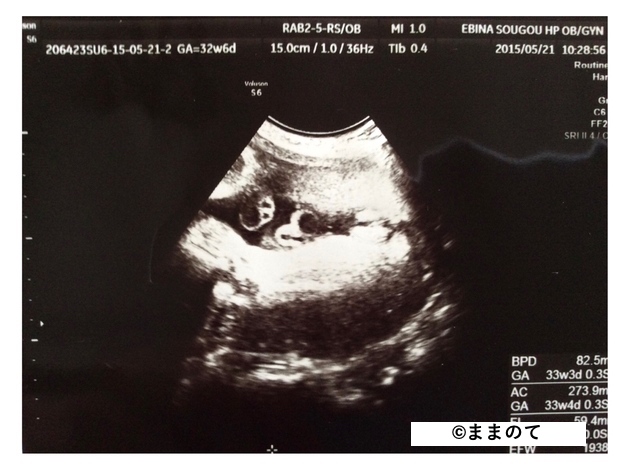

妊娠9ヶ月(32・33・34・35週)

このころの身長は約45cm、体重は2,000~2,400gになります。エコーでは全体像をとらえることが難しく、エコー写真には赤ちゃんの身体がアップで写し出されます。鼻や目などのパーツがくっきりと見えることもありますよ。

大腿骨や腹部の断面図だと、後で見たときにどこを写したのかわかりづらいため、写真を受け取る際に医師に確認しておくと良いでしょう。